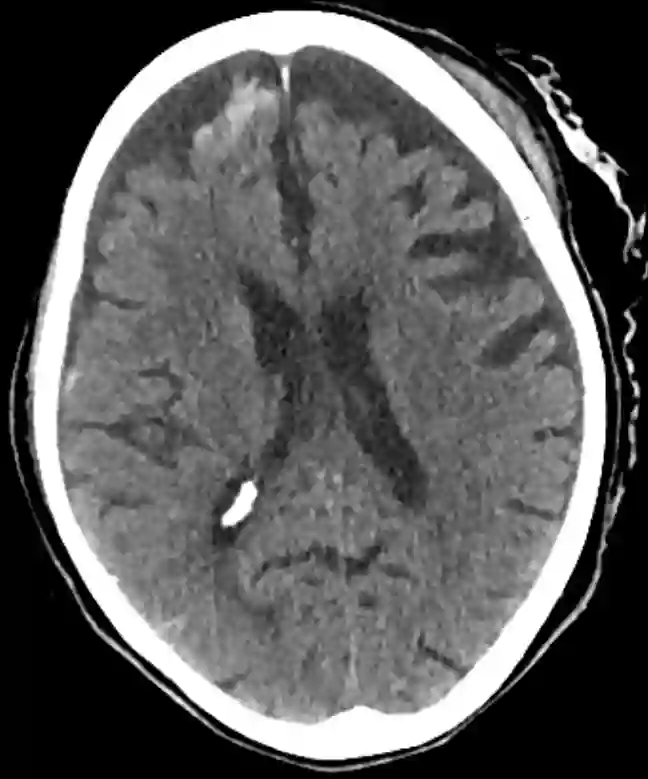

Traumatische Subarachnoidalblutung im CT

Traumatische Subarachnoidalblutung frontal rechts im CT.